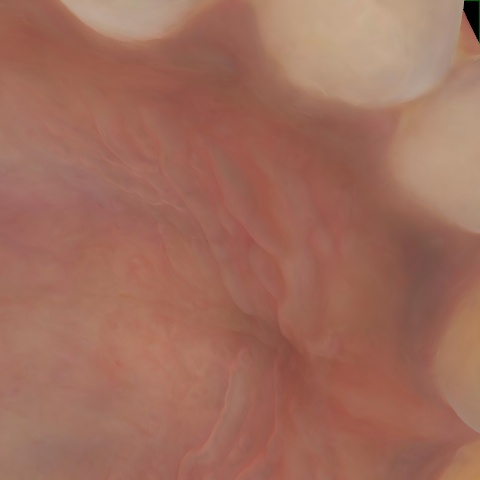

NHD39174

Annotated as "Good"